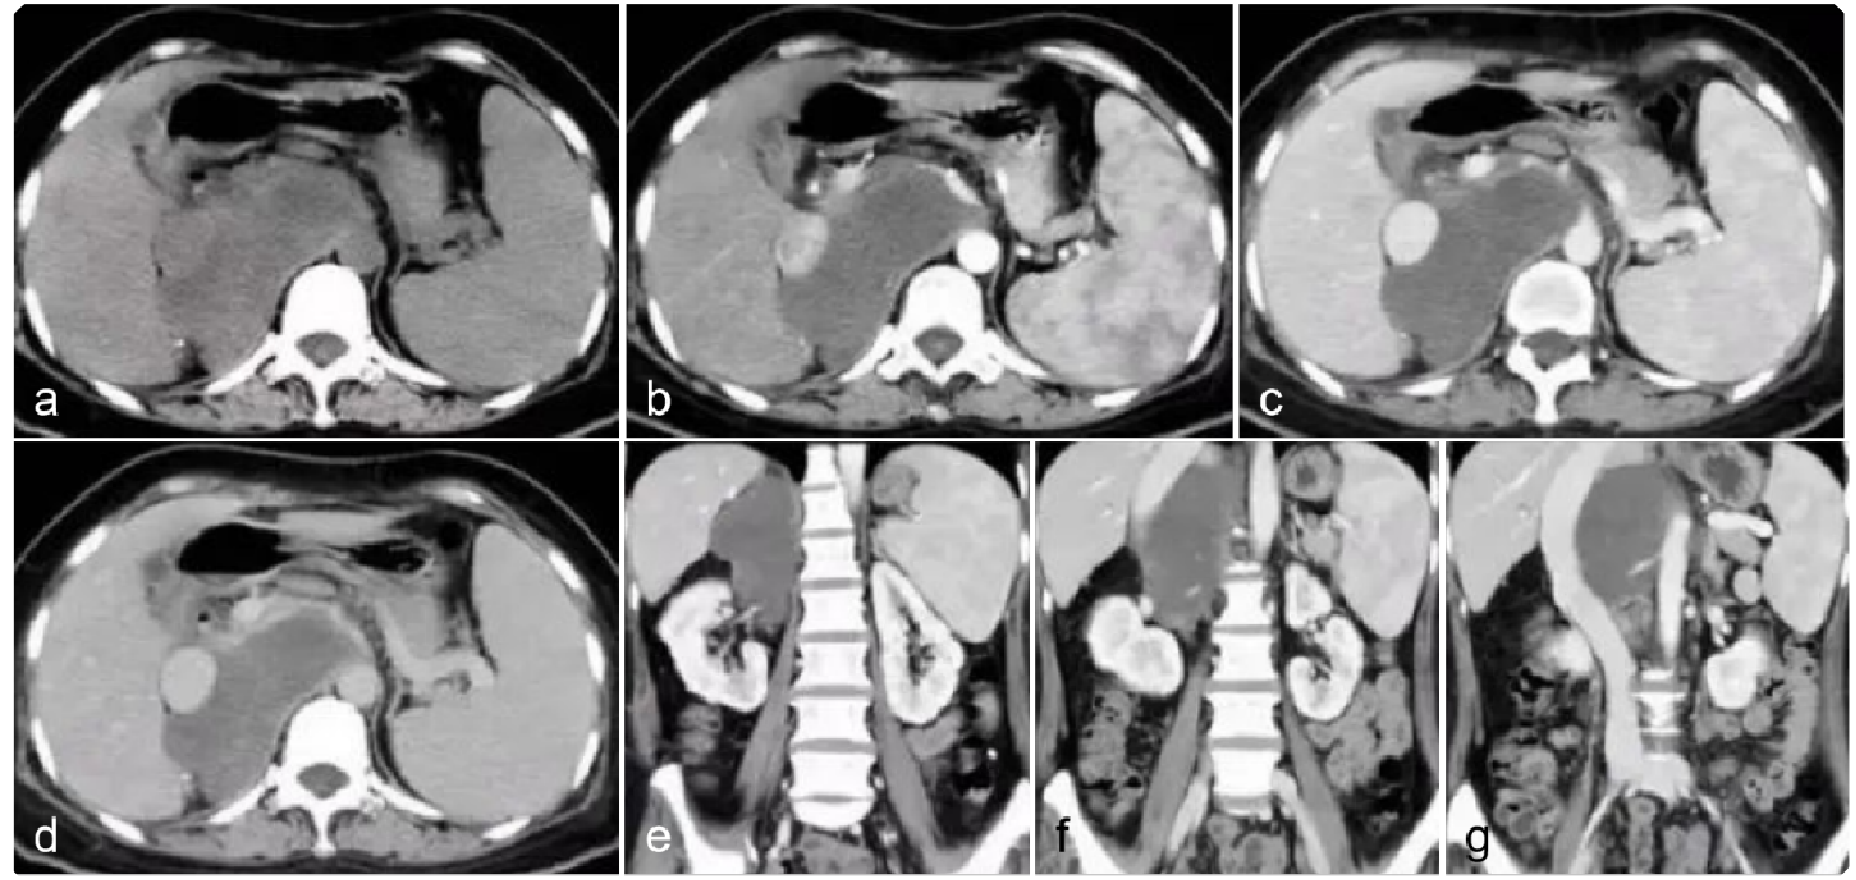

e6b157565c20beba067400577029f65f.png 病例 7:腹膜后(血管外)平滑肉瘤1例

增强CT(横、冠、矢状位)(a、b) 增强扫描动脉期与增强扫描静脉期;(c、d) 冠状位与矢状位影像。腹膜后单发肿瘤,体积较大,边缘规则的软组织肿块,有包膜,内密度不均匀,多发低密度灶;增强扫描,不均匀轻中度强化,内有不强化中心坏死灶与囊变区,门脉期较动脉期强化明显。增强扫描呈轻度渐进性强化,没有明显钙化灶,周围无明显肿大淋巴结。